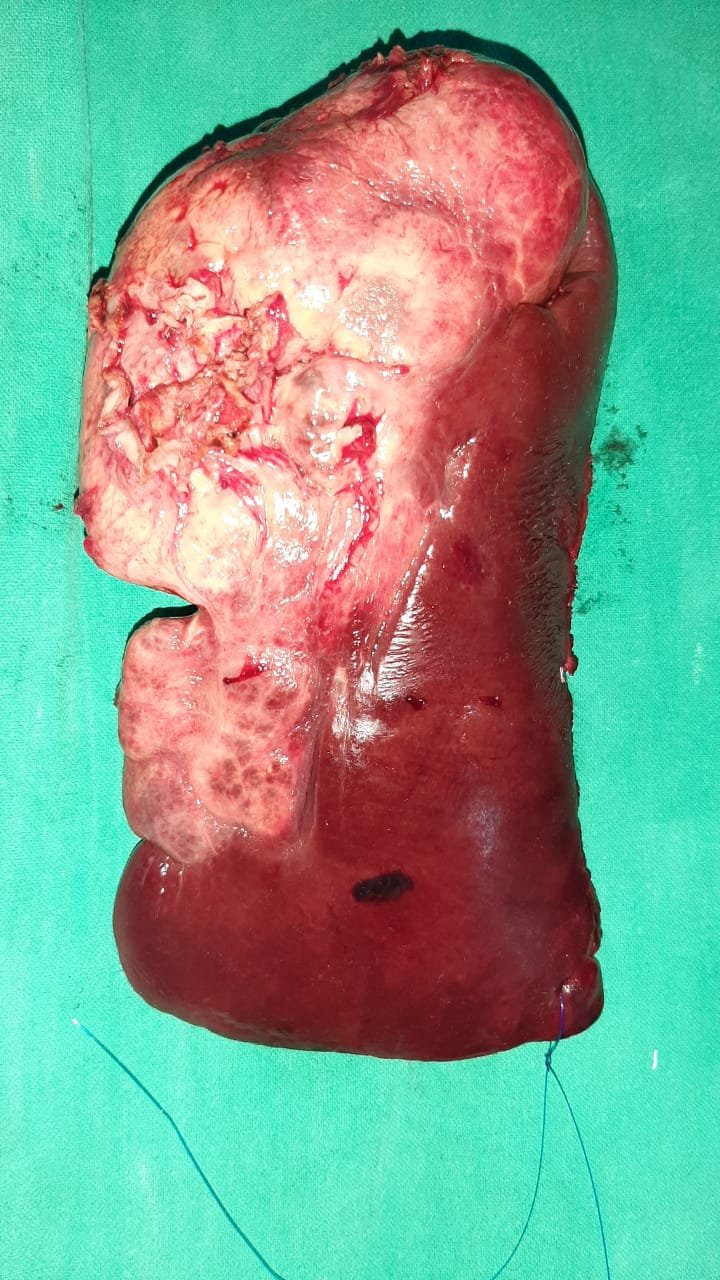

Liver is also unique anatomically as it looks one organ from outside it is divided in 8 segments and has 4 different type of vessel systems running inside. Removing a part of liver without damaging the function of remaining part, requires a great planning surgical precision, advance instruments and lots of experience.

Liver Surgery performed was right hepatectomy for hepatoblastoma in seg 6,7 and 8 of liver; in 11 year old girl in SMS Hospital, Jaipur